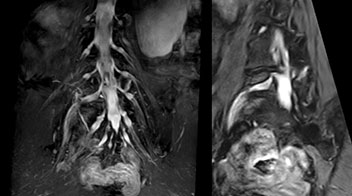

At Northern Fukushima Medical Center in Japan, excellent MRI visualization of nerves helps support confident diagnoses and informs surgical treatment decisions for patients with lower limb symptoms. MRI technologist Tanji and orthopedic surgeon Dr. Yabuki share how direct nerve visualization with the 3D NerveVIEW method adds information when diagnosing atypical herniations. The additional insights changed their way of working and benefit their patient care, as illustrated by some clinical examples.

“In patients with lower extremity neurological symptoms, NerveVIEW helps us to determine the disease matching the patient’s symptoms by directly visualizing the nerves. We use the sequence mainly, when there is suspicion of intraforaminal stenosis, extraforaminal stenosis or lateral disc herniation, which is often based on routine T2- and T1-weighted images. Additionally, the excellent depiction of the course of nerves makes NerveVIEW a good navigator when applying treatment such as block therapy or surgery.”

“In such case, we would then browse through axial T2-weighted MR images slice by slice and mentally reconstruct the actual situation based on both radiculography and MRI. Fortunately, NerveVIEW can now very well show nerve courses and presence of nerve compression or edema in one single image series.” “We have often seen NerveVIEW directly depict details of the nerve compression that were not observed by radiculography. Therefore, we think that with NerveVIEW we can reduce the number of invasive examinations, especially for some patients with lumbar plexus symptoms.”

“Before NerveVIEW, diagnosis by MRI alone was sometimes difficult, unless there was a strong suspicion based on clinical symptoms,” says Shoji Yabuki, MD, DMSc, Orthopedic surgeon at Fukushima Medical University School of Medicine. “This is why we routinely perform selective lumbosacral radiculography (nerve root block) and x-ray in such cases. However, radiculography can only depict nerves as far as the contrast agent reaches. When a nerve is distorted by compression, the contrast agent will not pass through this compressed area, preventing us from evaluating the full nerve compression.”

The key concept in MR neurography, Dr. Yabuki stresses, is the ability to directly visualize spinal nerves, versus inferring the presence of pathology indirectly. “Before NerveVIEW, we estimated compression of the nerve by looking for the presence or absence of fat signal on other MR images,” he says.

“For example, in sagittal images, when the presence of fat is observed in the intervertebral foramen, it suggests that there is a margin around the nerve. Similarly, the absence of fat indicates that the nerve is being compressed. So, we used to deduce nerve compression indirectly. With NerveVIEW, however, we can observe the condition of the nerves directly, regardless of the presence or absence of fat. We always prefer such direct observation of anatomy over having to make an inference about it.”

“Although symptoms of typical disc herniation and atypical hernia are very similar, the actual site of herniation is different. It is therefore important to characterize the nerve’s condition both inside and outside of the intervertebral foramina. “Conversely, if we see no abnormality in NerveVIEW, we can assume at least that there is no severe condition that requires surgery. Like this, it can help us avoid unnecessary surgery. NerveVIEW can have a tremendous impact in this way.”

“NerveVIEW is really useful for those cases where a nerve disorder is strongly suspected based on the clinical examination but our regular MRI images do not show any findings. These atypical herniations and spinal canal stenosis, occurring in 5% to 15% of the total lumbar herniation/stenosis cases are our main target when using NerveVIEW,” says Dr. Yabuki.